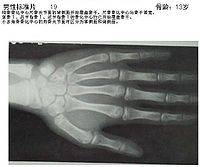

人的生长发育可用两个“年龄”来表示,即生活年龄(日历年龄)和生物年龄(骨龄)。骨龄是骨骼年龄的简称,借助于骨骼在X光摄像中的特定图像来确定。在了解人的骨龄情况时,通常要拍摄人左手手腕部的X光片,医生通过X光片观察左手掌指骨腕骨桡尺骨下端的骨化中心的发育程度,来确定骨龄。

传统的骨龄评估通常是对被测者的手部和腕部进行X光摄片,然后由医生根据拍得的X光片进行解读。解读的方法有简单计数法、图谱法、评分法和计算机骨龄评分系统等,最常用的是G-P图谱法和TW2(TW3)评分法;根据骨龄预测成年身高包括B-P法、RWT法、TW2法等。